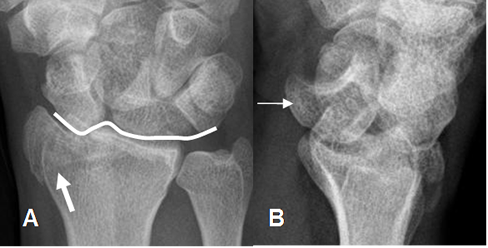

Fig 41. Desalineación del carpo.

A: Rx AP. Arco I del carpo mal alineado, por lesión. Adicionalmente hay fractura del radio. (Flecha gruesa).

B: Rx lateral. Se confirma luxación del semilunar.